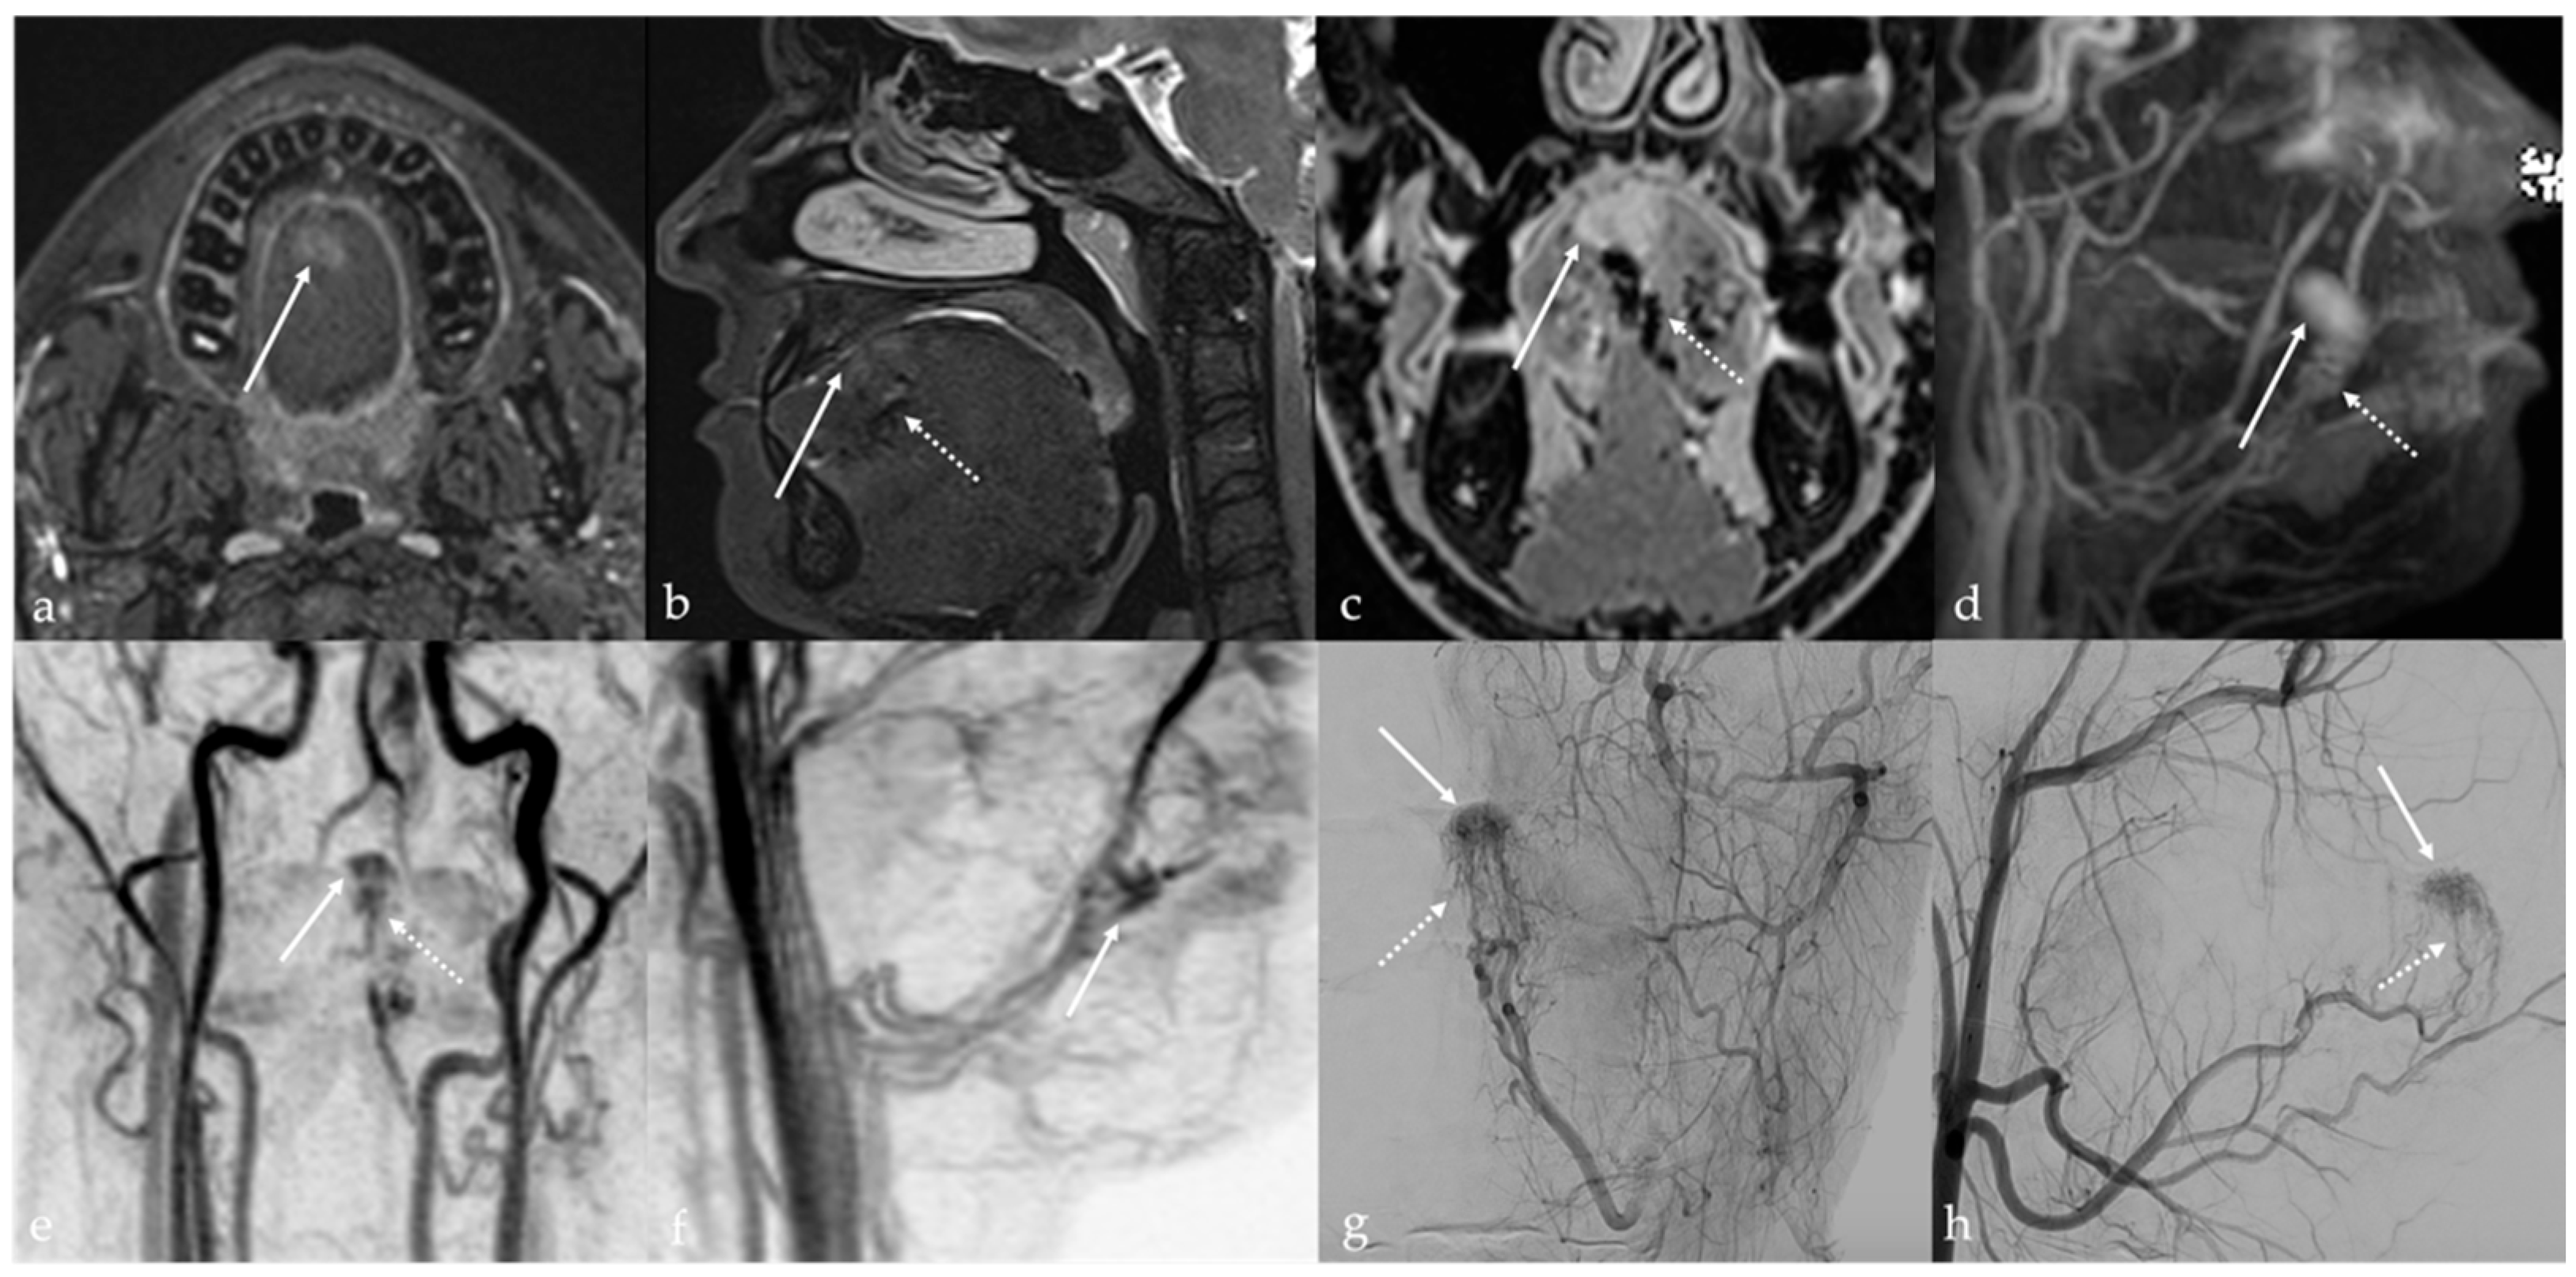

5.3. Arteriovenous Malformations

| Arteriovenous malformation [6,12] | MRA: arterial feeding vessel, nidus, and venous drainage vessels MRI: flow voids | Other vascular malformations |